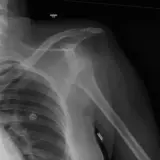

Over 2,100 interactive radiology cases, curated by radiologists for your level of training. Scroll, window, and view cases full screen โ€” just like on PACS. Click linked findings in each writeup to jump straight to them on the image. Cases include sample reports, a focused discussion section, original illustrations, and videos.

Casi completamente interattivi con gli strumenti che ti aspetti su un PACS: scroll, windowing, zoom, pan, misurazioni, ROI e modalitร  a schermo intero.

Annotazioni dettagliate evidenziano i reperti chiave direttamente sui casi. Clicca sui reperti collegati nella descrizione del caso per saltare alla loro esatta posizione sullo scan.